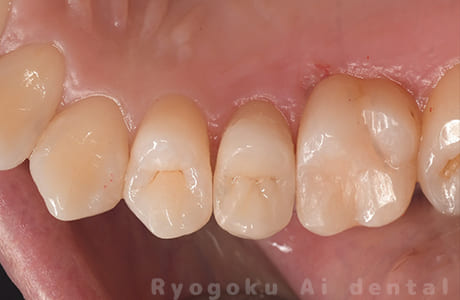

Case05

-

- 原因

- 15部重度カリエス

- 治療内容

- 断髄治療

- 治療費用

- 66,000円

歯がしみるとのことで来院された患者様です。虫歯が神経まで及んでいましたが、神経を一部分カットする断髄治療を行いました。経過も良好です。

<リスク・副作用>

術後は痛み、腫れ、痺れなどの副作用が生じる場合があります。症状が再発する可能性があります。その場合は抜髄する必要があります。